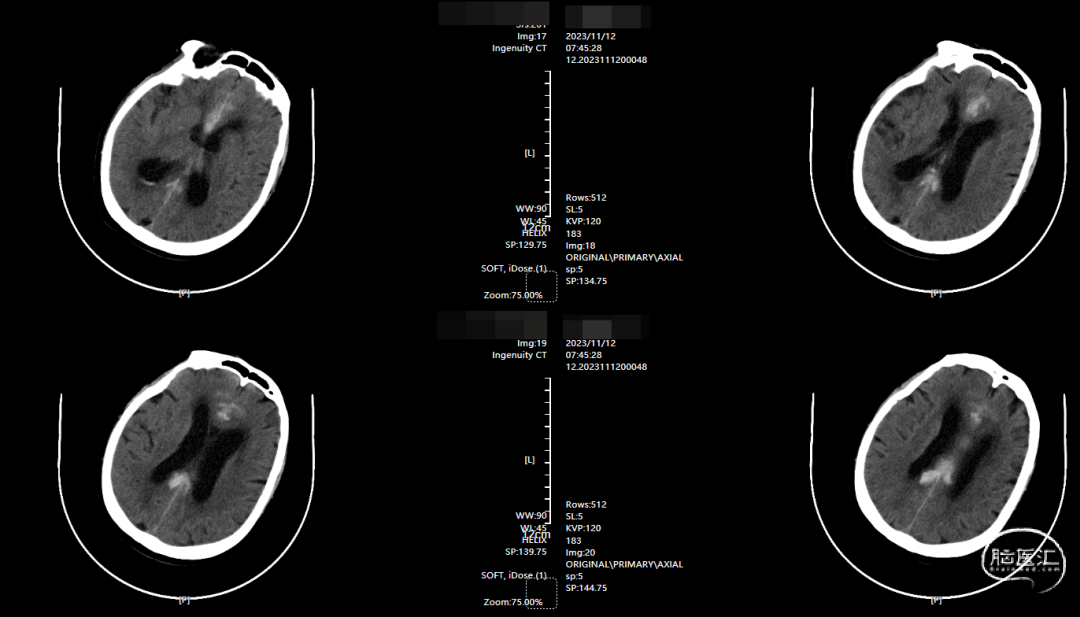

术前影像

CT示纵裂内血肿。